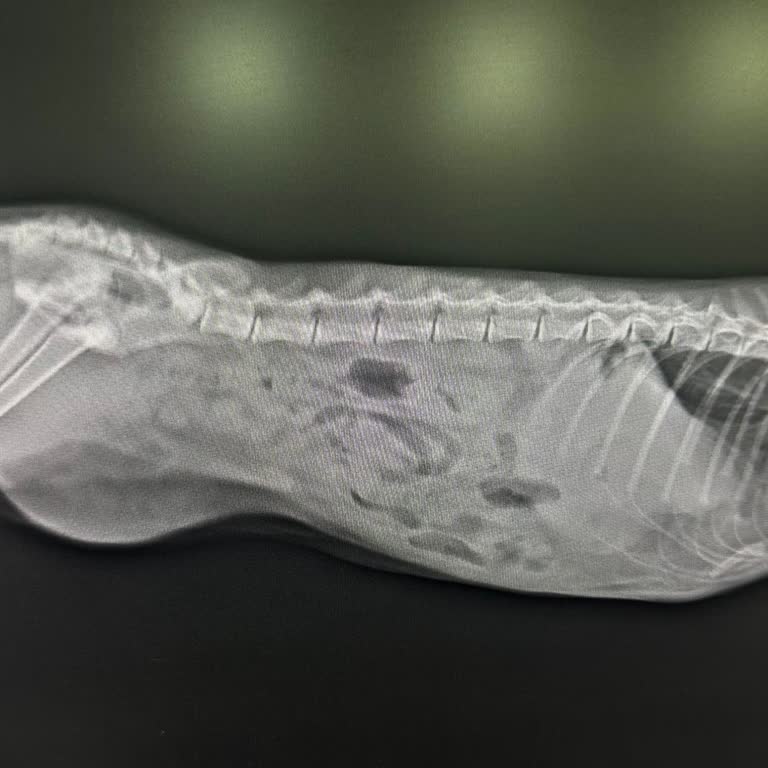

12.09.2025 tarihinde animal town veteriner kliniği Mecidiyeköy, naci kasım sk. **, 34000 Şişli /İstanbul adresinde bulunan kliniğe gittik. Sokakta baktığımız kedimizi sahipleneceğimiz için ön muayene yaptırmak istedik. Yavru kedimizin bir hafta önce darbe sonucu iç kanama geçirdiğini ve Eyüp Belediy...